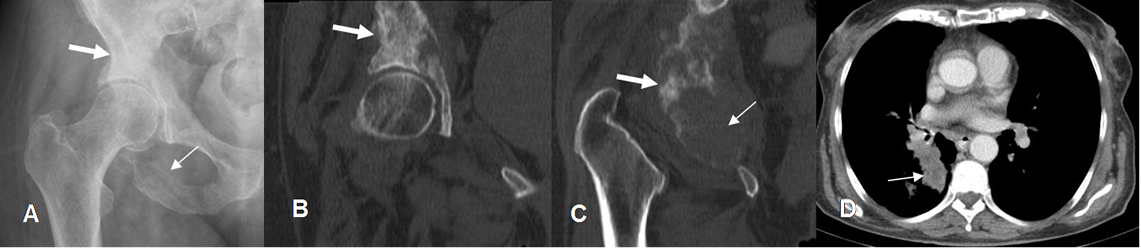

Fig 228 B. Metástasis mixta.

A: Rx AP, B y C: TAC reconstrucción coronal y D: TAC axial de tórax. Lesiones líticas en el ramo isquiopúbico (Flechas delgadas) y blásticas en el acetábulo (Flechas gruesas), que rodean la cadera, correspondiendo a enfermedad metastásica de pulmón.